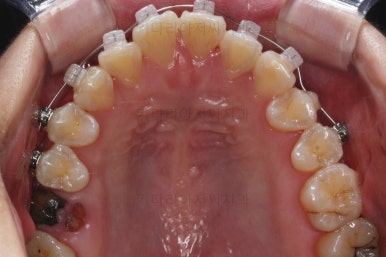

1. 초진

초진 시 입안의 모습입니다.

당장 눈에 띄는 부분은 아래 앞니 사이에 틈새가 있어 치석도 많이 쌓여있는 상황이고요.

윗니-아랫니를 각각 보면 치아가 썩고 부러져 뿌리만 남은 치아가 많이 보입니다.

남은 치아들도 곳곳에 충치가 보이고요.

또 전반적으로 앞니가 앞으로 밀려나와 뻐드러져 있는 모습도 관찰되네요.